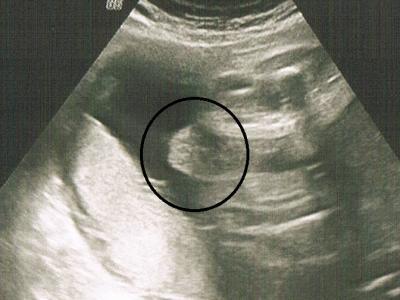

Was meint ihr? Ist es ein Junge oder ein Mädchen auf dem Ultraschallbild? Meine FA wollte sich nicht festlegen...

Die FA sagte zuerst, dass es ein Mädchen sein könnte und sie die Schamlippen sieht. Dann sagte ich ihr, dass eine andere FA bei der Feindiagnostik eher einen Jungen erkannt hat. (aber sie sah auch"nur" Hoden) Dann wurde die andere FA plötzlich ganz unsicher und sagte, dass es auch Hoden sein könnten.